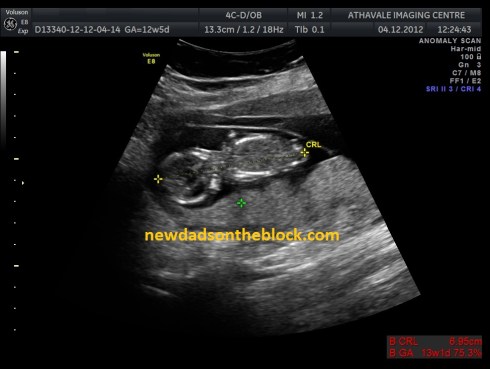

As of this weekend, our twins are fourteen weeks along.

From what we’ve read, that means the babies are likely about 3.5-4” each, crown-to-rump-length, and each probably weigh about two ounces.